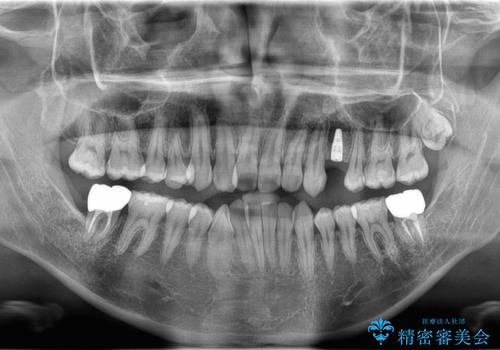

歯を保存するのは出来ないと診断し抜歯した後にインプラントで治療を行いました。

- 440,000円(インプラント体220,000円+カスタムアバットメント110,000円+オールセラミッククラウン110,000円)費用は治療当時の料金となります

長い間虫歯を放置していたため、根っこだけになっている状態でした。このままでは被せ物を被せられないため抜歯を行い治癒を待った後にインプラントを埋入しオールセラミッククラウンで治療を行いました。